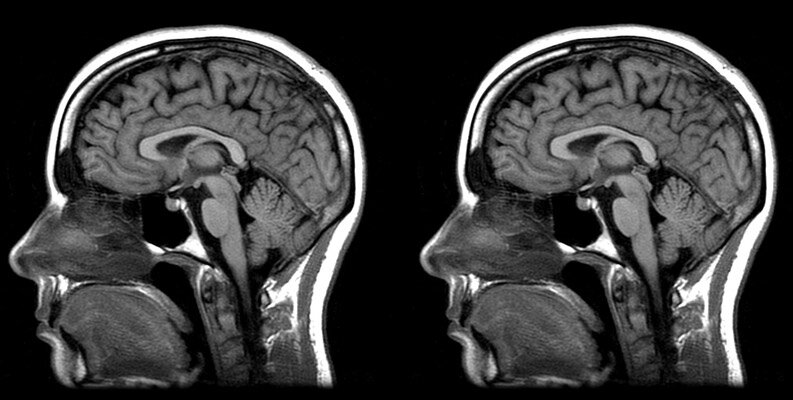

6. В 2002 году в Америке 7-летней девочке сделали операцию, в ходе которой было удалено все ее левое полушарие головного мозга. Операция была необходима, потому что у девочки был хронический энцефалит, который угрожал ее смерти. Как мы знаем, левое полушарие отвечает за речь и другие важные функции организма, поэтому можно ожидать, что после операции будет нарушена способность общаться и двигать тело. Оказалось, однако, что ребенок полностью нормален и свободно говорит на двух языках. Это показывает, насколько невероятен человеческий мозг. Если какой-то участок мозга поврежден, другой может взять на себя его функции.

10. Мозг женщины меньше мозга мужчины. Однако это не сопровождается разницей в эффективности. Вот и получается, что у женщин мозг немного эффективнее, чем у мужчин.